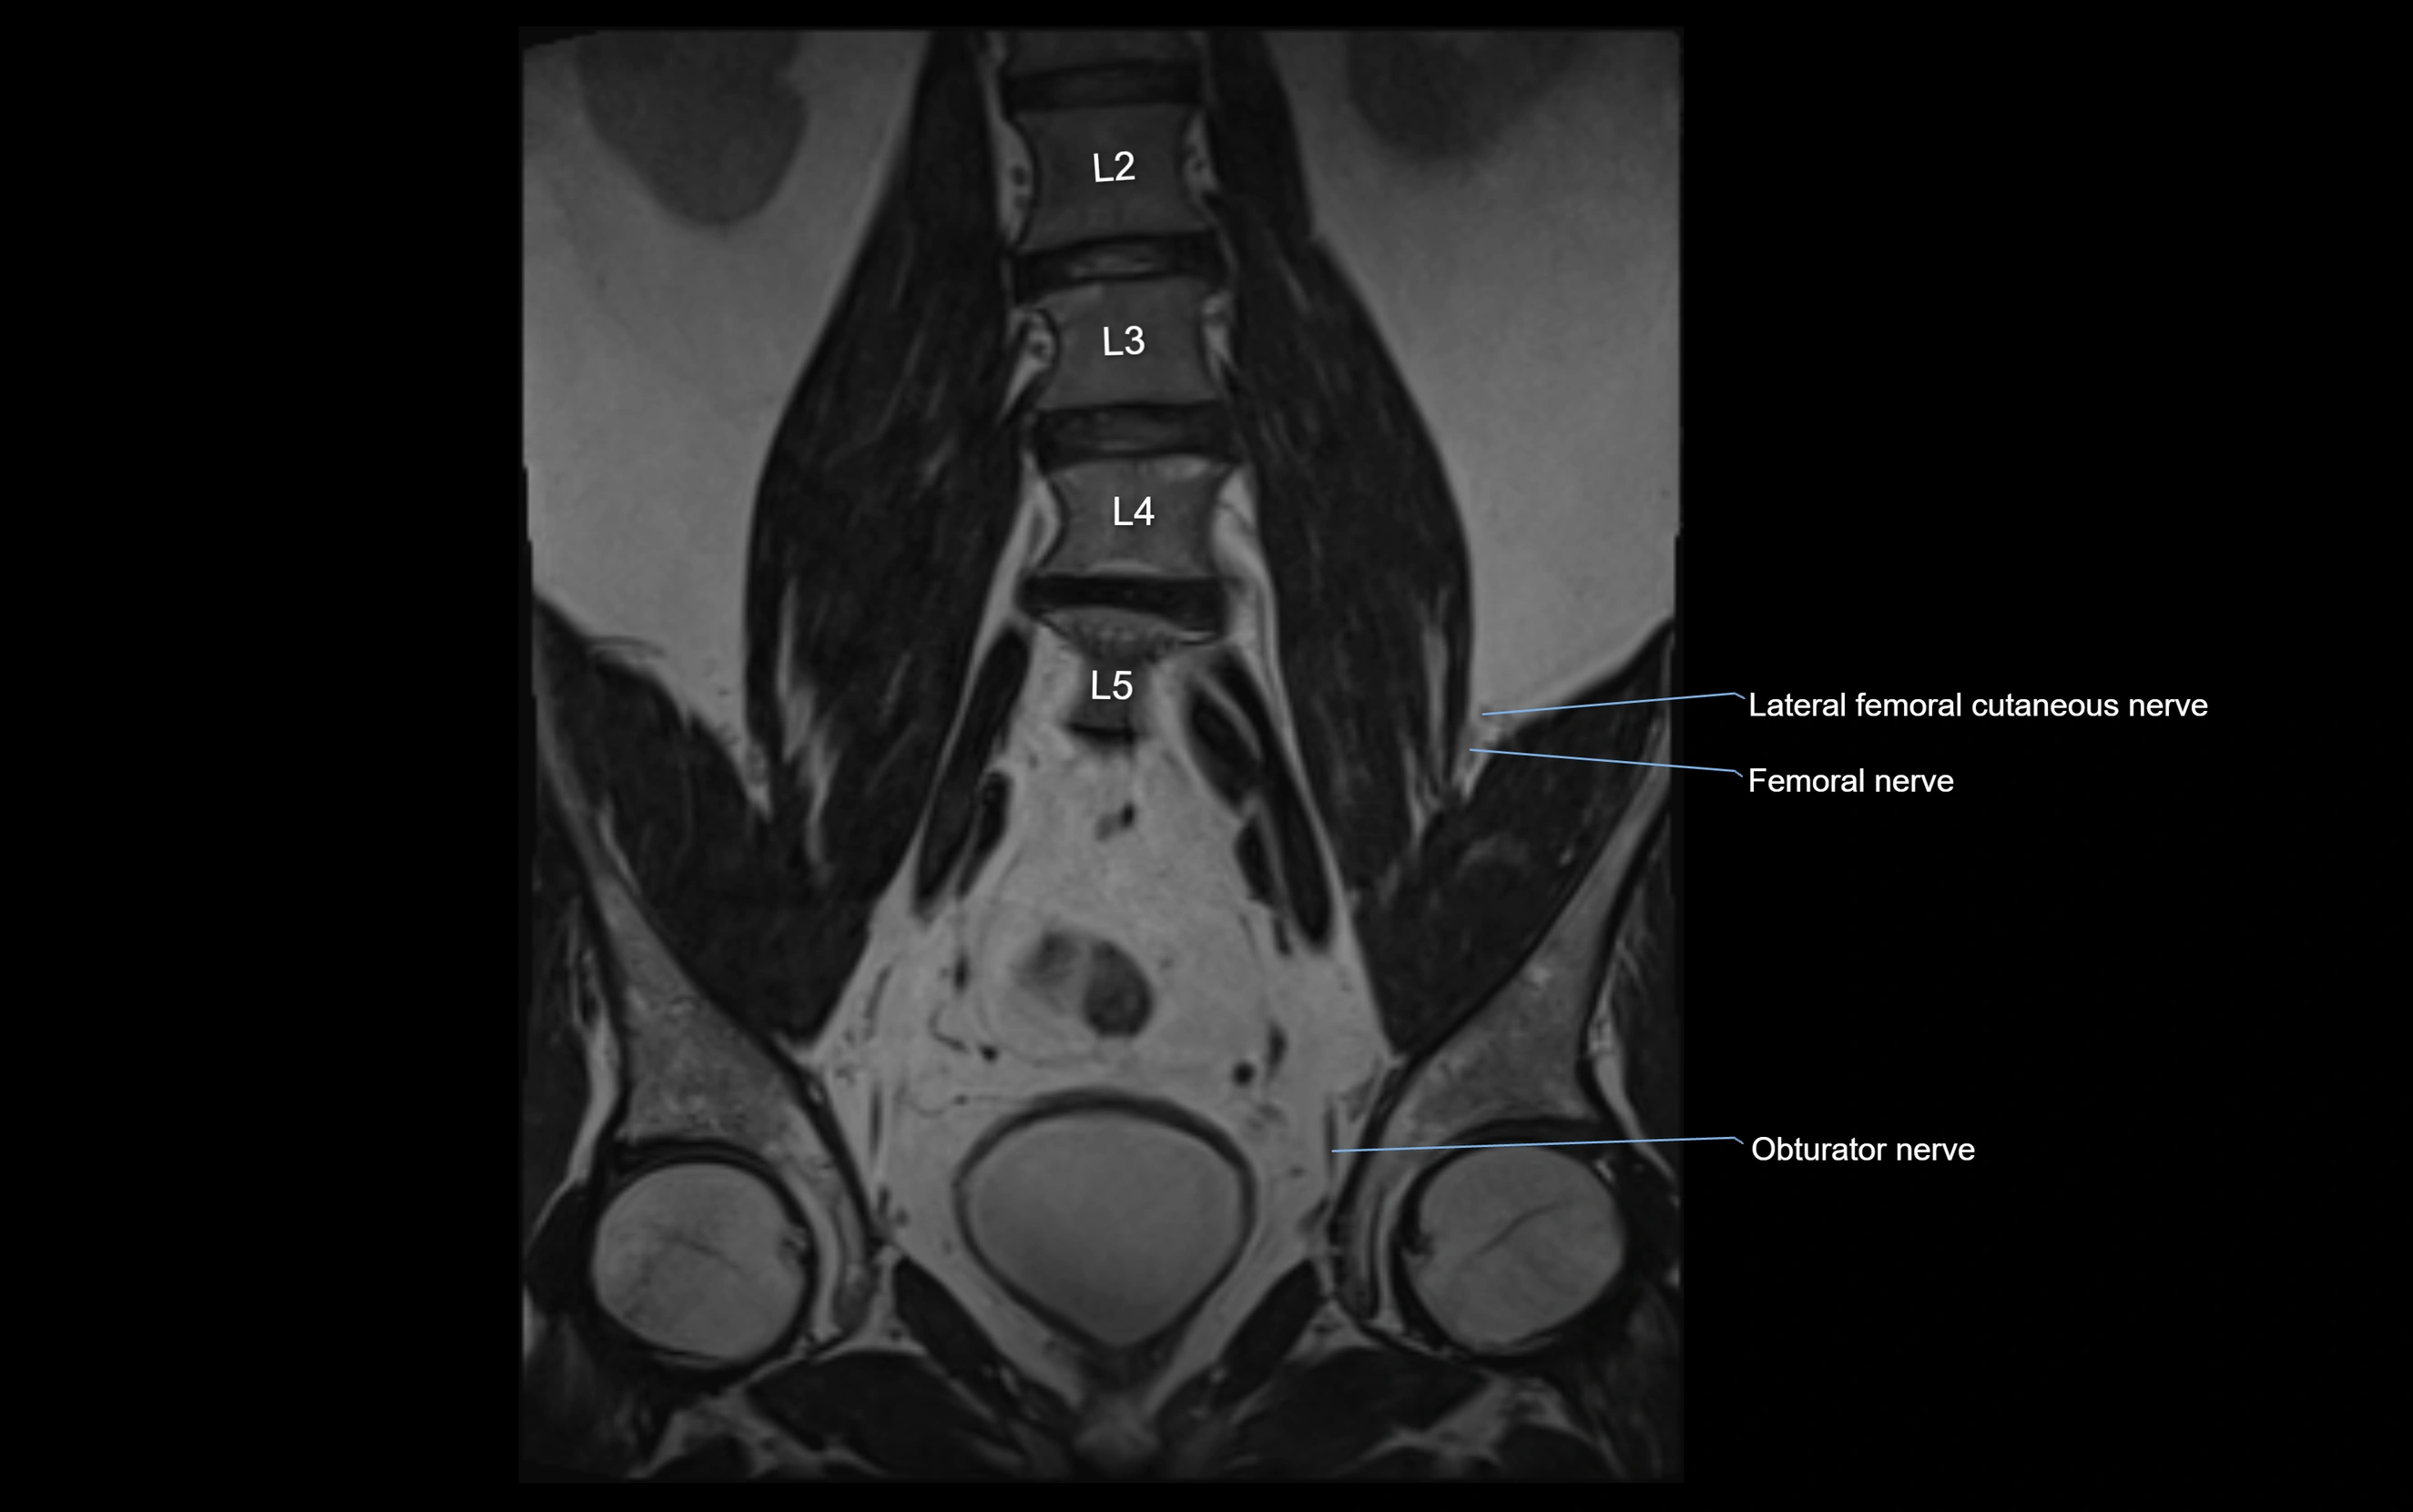

MRI Appearance

T1-weighted images:

• Nerve appears as a very thin low-to-intermediate signal intensity structure

• Surrounded by bright fat, aiding visualization

T2-weighted images:

• Nerve shows intermediate to mildly hyperintense signal compared to muscle

• Pathological involvement appears brighter

STIR (Short Tau Inversion Recovery):

• Normal nerve appears dark

• Inflamed or entrapped nerve appears bright hyperintense

T1 Fat-Sat Post-Contrast:

• Normal nerve enhances minimally

• Pathologic nerve (neuritis, entrapment, tumor infiltration) shows focal or diffuse enhancement

3D T2 SPACE / CISS:

• Nerve appears intermediate to mildly hyperintense compared to muscle

• Surrounded by bright fat or CSF, improving visualization

• Best sequence for mapping small pelvic nerves such as the anococcygeal